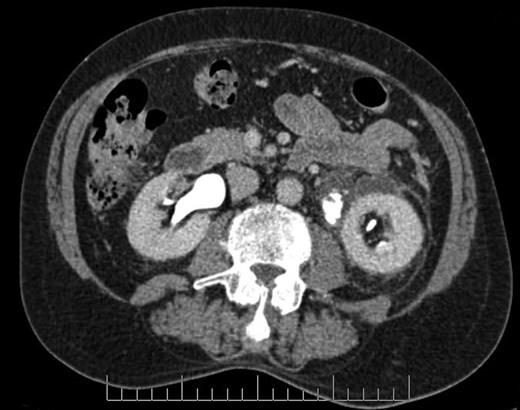

Axial section CT image demonstrating defect in left proximal ureter from which contrast is extravasating, with perinephric fluid collection and fat stranding.